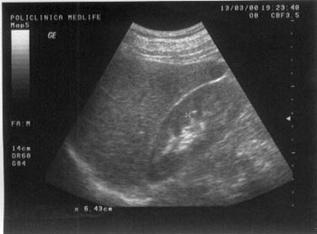

Figura

14. Mas[ gigant[ care ocup[ micul bazin =i abdomenul mediu, de aproximativ

30 cm diametru, cu structur[ complex[ 80% lichidian[, restul solid[. Partea

solid[ este dispus[ sub form[ de septuri. Aspectul sugereaz[ histademom cu

apartenen[ ovarian[.